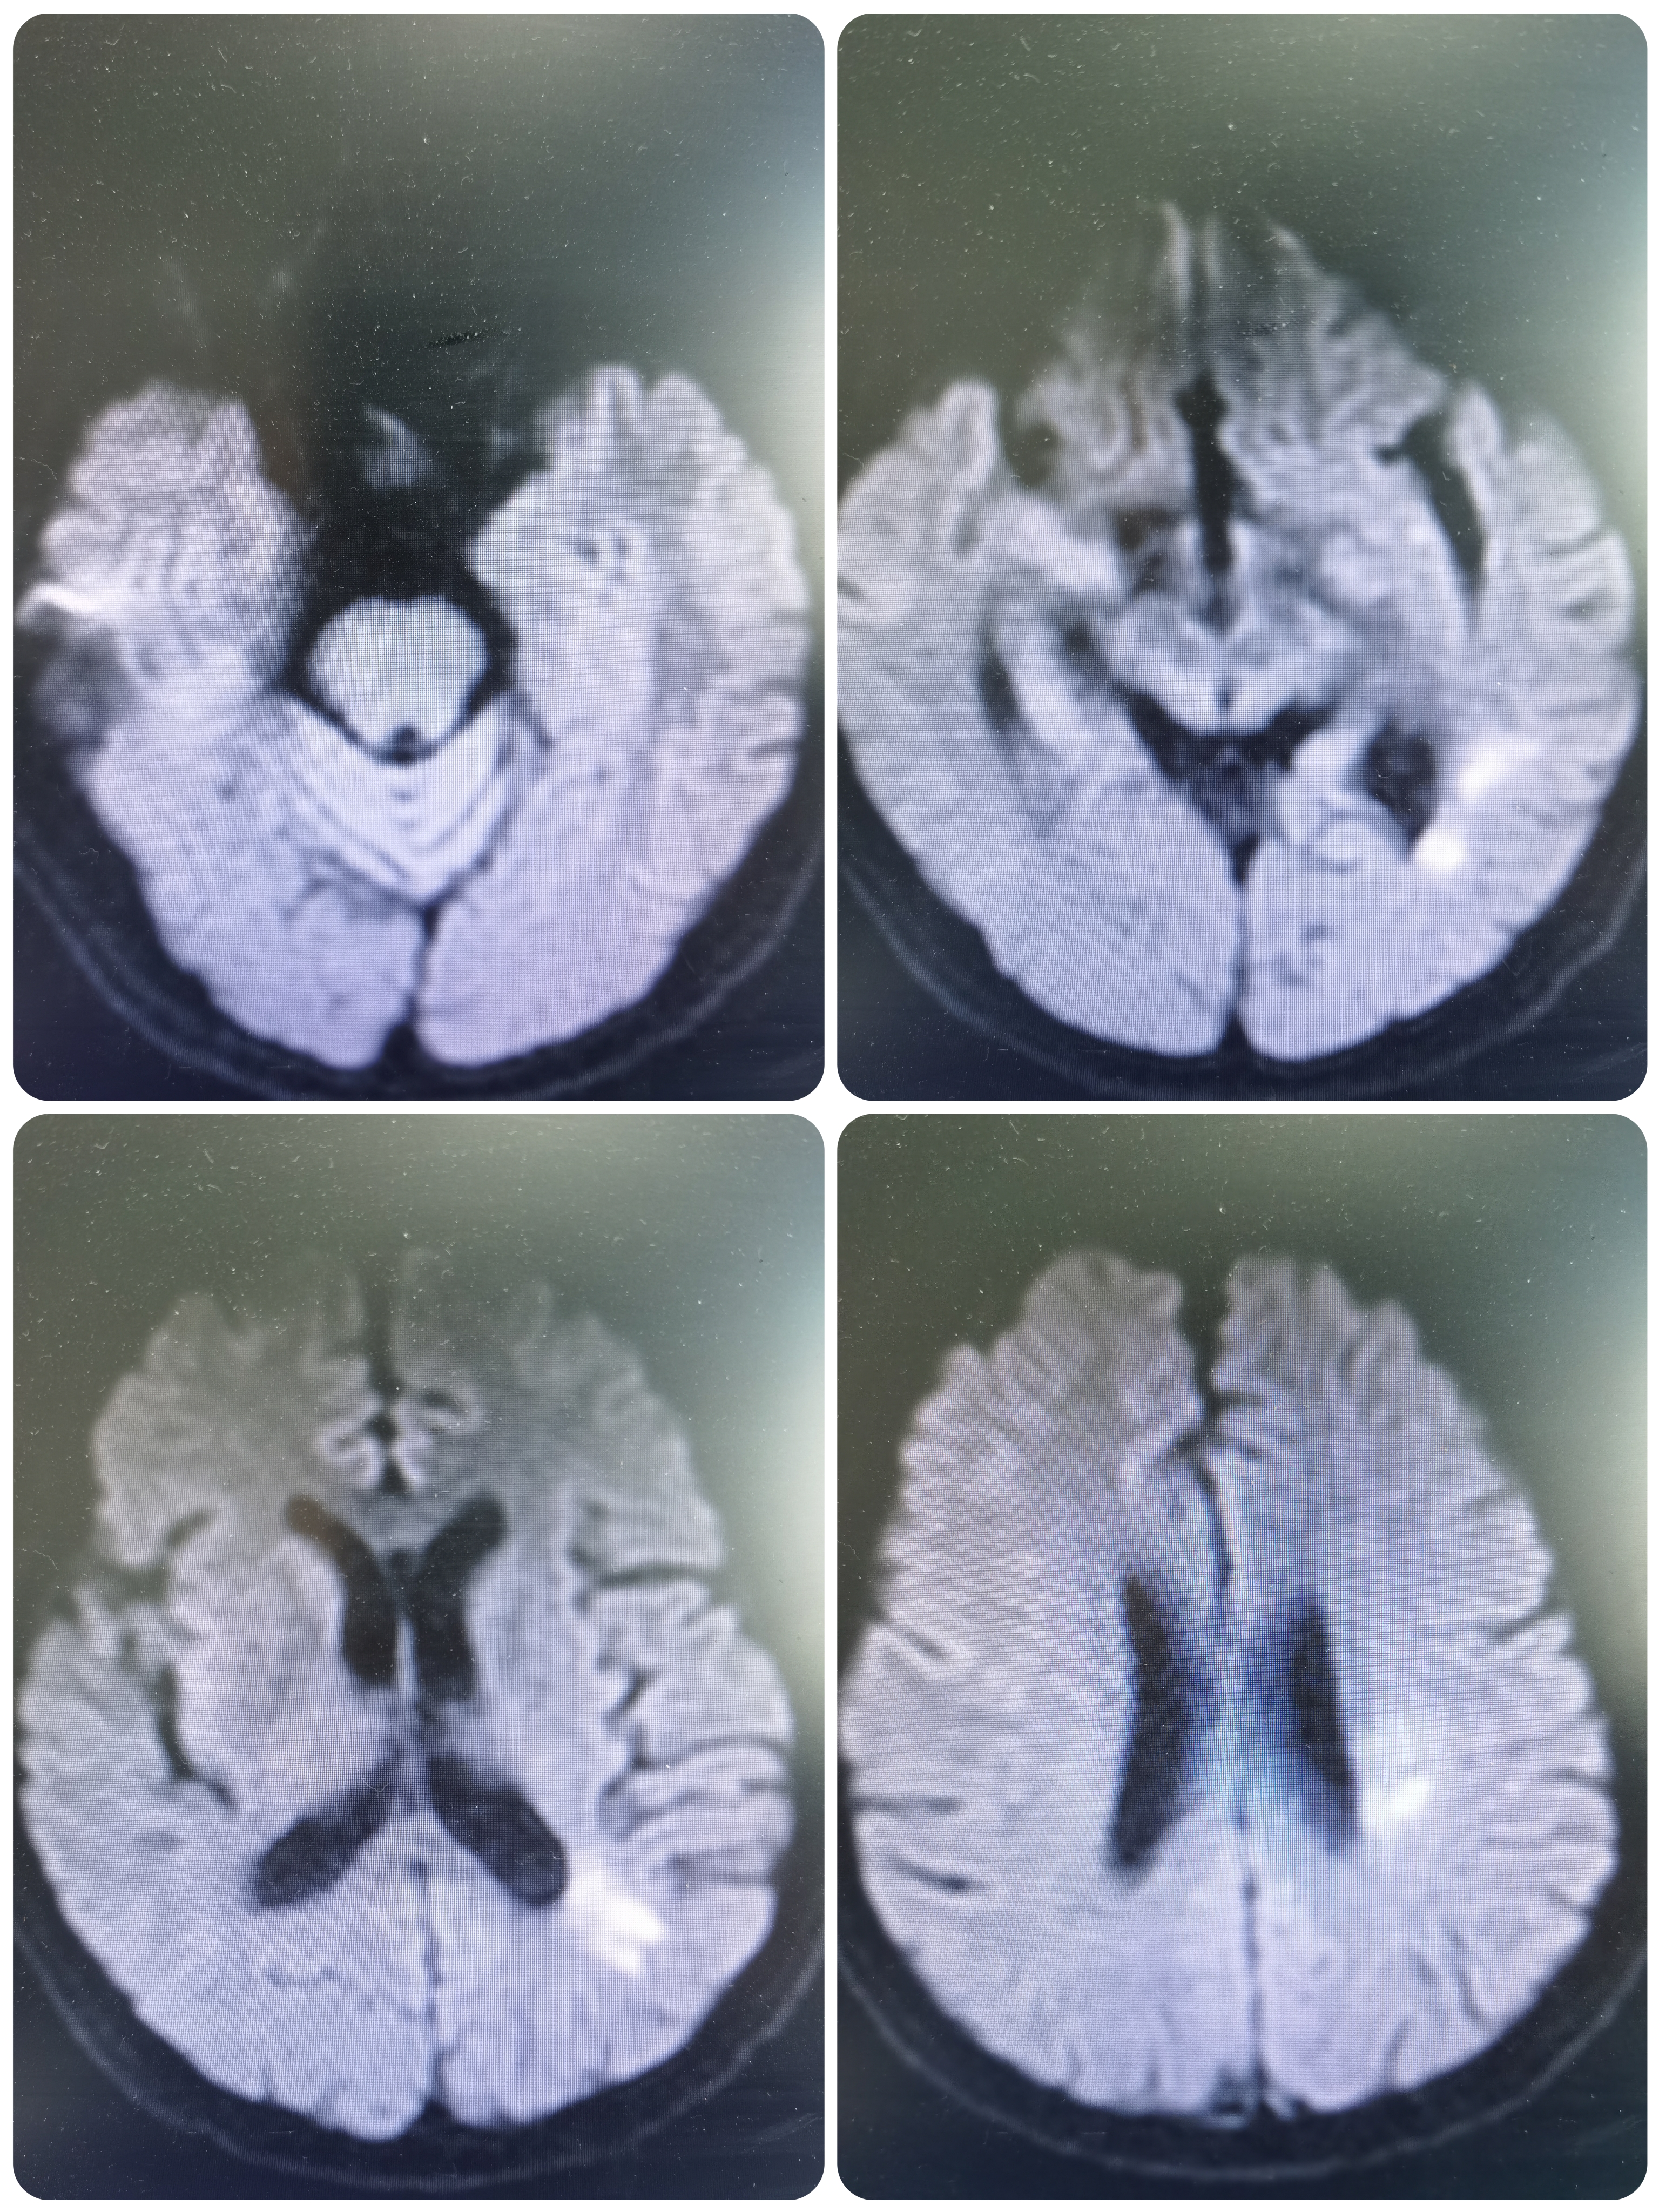

核磁DWI示左侧脑室后角及左侧侧脑室旁新发脑梗死。

MRA示左侧大脑中动脉M1闭塞。

患者新发脑梗死,MRA示左侧大脑中动脉闭塞,系责任血管,发病超过1周,遂先给予双联抗血小板,强化他汀及改善循环治疗,经治疗后患者症状稳定,并进一步完善血管学检查。

CTA示左侧大脑中动脉闭塞。